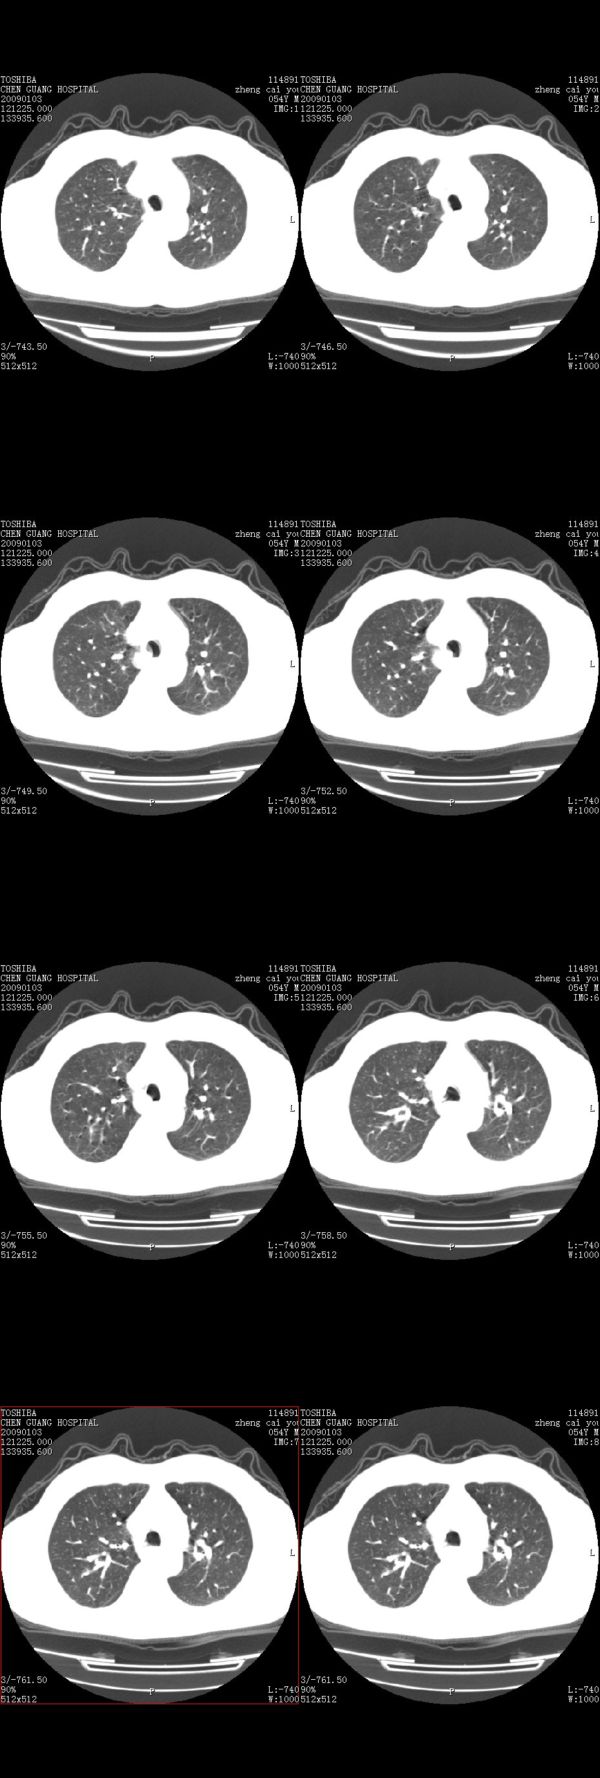

男,54岁,平时有吸烟后咳嗽、咯痰史,因右侧胸部(腋窝下)疼痛来检查平片,见右下肺动脉干起始处处结节,后到同学处做了平扫及增强。请各位老师帮忙看一下,不甚感谢!!!!!

多为血管断面影;建议必要时行ct增强扫描检查。

没有纵膈窗,也没有增强,确实不好说。从连续层面来看像是血管影。不放心做个强化最好了,毕竟是自己最亲的人!!

增强了 但纵隔窗调的看不清  右上叶支气管壁似有增厚 警惕

肺窗薄扫、常规扫描均未见明确病变;右下肺门圆形与肺血管等密度影,考虑为血管变异;应该要纵隔窗才能进一步明辨。

主要应该看一下纵隔窗,感觉到右肺门的血管有局限性的扩张,呈结节状,再做个增强ct扫描.